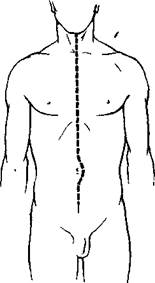

Прозектор становится справа от трупа и сохраняет ату позицию во все время вскрытия. Левше удобнее стоять слева от трупа (рис. 26).

Малым секционным ножом делают основной разрез (рис. 26) от подбородка до лобка по срединной линии, обходя пупок с левой стороны трупа, чтобы не повредить круглую связку печени. Секционный нож при этом нужно держать горизонтально, захватив рукоятку его в ладонь, и резать не концом, а брюшком лезвия (см. рис. 2 на стр. 23).

| Рис 26 Основной разрез стенки туловища. |